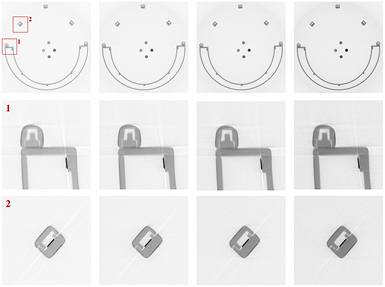

Figure 2. Upper left: Siemens Trio 3T MRT with BrainPET insert and dedicated head Tx/Rx coil. Upper right: detailed view of the Tx/Rx head coil. Lower left: head coil holding extension for the patient bed of the Siemens Trio 3T MRT with BrainPET insert. Lower right: head coil holding extension together with Tx/Rx coil.

Download figure:

Standard image High-resolution imageFigure 3. View field for the uppermost PET cassette (grey with green frame) together with the 19 opposed PET cassettes (solid green) for which coincidences are accepted. The red sectors mark the missing projections for this cassette. A transversal CT image of the Tx/Rx coil is superposed to show which parts of the coil fall outside the transversal FOV.

Download figure:

Standard image High-resolution image2.1. Scanner stability

Figure 8 shows one slice of each of the four CT images from the Tx/Rx head coil and the material samples acquired with the four different x-ray tube configurations resumed in table 1. Only very weak streak artefacts, as reported from images acquired with a clinical CT scanner (for instance MacDonald et al 2011), were visible in these images. This is because the x-ray photon energy of the industrial CT scanner is higher and, during coil design, special emphasis was put on avoiding the placement of heavily attenuating components inside the FOV of the MR-BrainPET. The antenna components, made from copper ribbons, can be identified as 8 thin short dark lines arranged in a circle around the image centre. Due to the very small size of the copper elements inside the FOV, it can be assumed that the x-ray and γ-ray attenuation is mainly caused by the carrier material. In figure 9, ratios of the mean intensity values for the different VOIs and the mean grey value of the water VOI are shown. It can be seen that, within the measurement errors, the coil material has the same x-ray attenuation as water. Although we do not know the exact composition of the coil material, we conclude that a water equivalent plastic was used as carrier material. Knowing the material composition of the coil, the ACF values for 511 keV could have been obtained from the ACF values measured with the 176Lu activity using equation (3), had the path lengths traversing the coil and the surrounding air for each LOR been known. However, as explained in section 2, reconstruction of the attenuation map was not possible because of missing projections (see figure 3). By using equation (4), we estimated the error for the ACF values as if the coil material was water and the ACFs were not corrected for the different γ-ray energies. For structures not larger than 6 cm, which is the case for the Tx/Rx head coil used, we obtained an error for the ACF that was not larger than 28% for a γ-energy of 202 keV and not larger than 14% for a γ-energy of 307 keV. With the MR-MR-BrainPET, offline energy discrimination is not possible in normal operation mode, but according to Rothfuss et al (2014), 61.6% of the recorded counts during a transmission scan with 176Lu background arise from the 307 keV photons and 38.4% from the 202 keV photons, whereas 88 keV photons were rejected. Therefore, it can be assumed that the maximum ACF errors are closer to 14%. Plots of ACF errors for several thicknesses without applying energy extrapolation are shown in figure 10.

Figure 8. Upper row: single CT image-slices of Tx/Rx head coil and four material samples. Middle and lower row: detail views of support structures and conductors. From left to right:  keV,

keV,  keV,

keV,  keV, and

keV, and  keV. Material samples: upper is PVC, right is PTFE, lower is PMMA, left is water. Lowered CT image contrast at higher energies is clearly visible.

keV. Material samples: upper is PVC, right is PTFE, lower is PMMA, left is water. Lowered CT image contrast at higher energies is clearly visible.